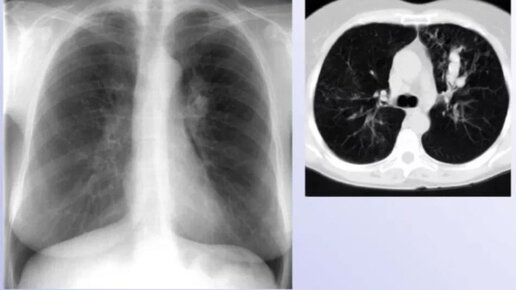

Периферический рак легкого. Бессимптомная опухоль размером почти 4 см. Для ранней диагностики рака легкого крайне важно ежегодное обследование. В России более 60 тыс случаев рака легкого в год.